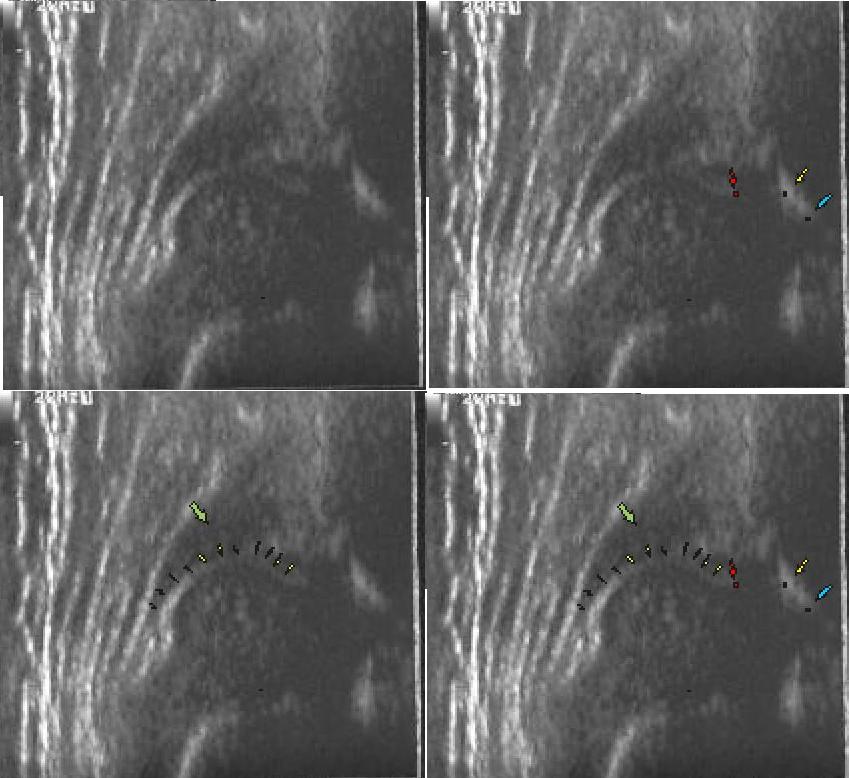

powyżej staw prawidłowy Typ I dach kostny dobry;brzeg kostny tępy ;dach chrzestny pokrywa

dolne zdjęcia

strzałki pokazują obrabek(czerwona):brzeg kostny (żółta);gałąż dolna(niebieska) ,

prawidłowy przebieg linii dachu kostnego(niebieska) stycznie do echa gałęzie dolnej i echa brzegu kostnego ;

linii dachu chrzęstnego (czerwona) stycznie do brzegu kostnego i przez środek geometryczny obrąbka i

linii podstawnej ( żółta

typ I czerwone kropki(od lewej) pokazują punkty do kreślenia 1 środek geometryczny obrąbka 2.brzeg kostny;3.gałąż dolną kości biodrowej

Typ IIc czerwone kropki od lewej) pokazują punkty do kreślenia 1 środek geometryczny obrąbka 2.brzeg kostny(dwa punkty);3.gałąż dolną kości biodrowej

typIV powyzej zarys torebki zaznaczony kropkami widac charakterystyczna muldę głowa straciła kontakt z panewka, przesuneła sie w stosunku do niej doogonowo tzn szczyt paneki jest poniżej szczytu głowy

poniżej różnica między obrazem a pomiarem automatycznym kątów przez aparat usg

Typ D(kąt jak Typ IIa) typ IIA (kąt I) dziecko 3 tygodniowe pomiar katów @ i B przez program w aparacie usg

po następnej wyznaczonej kontroli za 2miesiące w 3m.ż typ IV i I